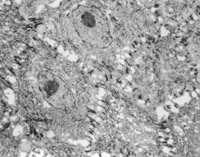

經(jīng)MEBT/MEBO治療20天,電鏡觀察到基底細胞層與纖維母細胞之間的半橋粒連接,同時可見纖維母細胞內(nèi)粗面內(nèi)質網(wǎng)結構和線粒體增生活躍(圖5-3-19~5-3-21)。 MEBT/MEBO治療30天后,上皮組織再生修復,已基本完成,創(chuàng)面組織切片顯示膠原纖維成熟,排列整齊(圖5-3-22),直徑為0.1~0.5祄,并可見明暗相間周期性橫紋(64nm),未見到膠原纖維扭曲和呈旋渦、菜花等病理形態(tài)。

5-3-20 粗面內(nèi)質網(wǎng)結構和線粒體增生活躍  TEM×17000

5-3-21 同上  TEM×20000